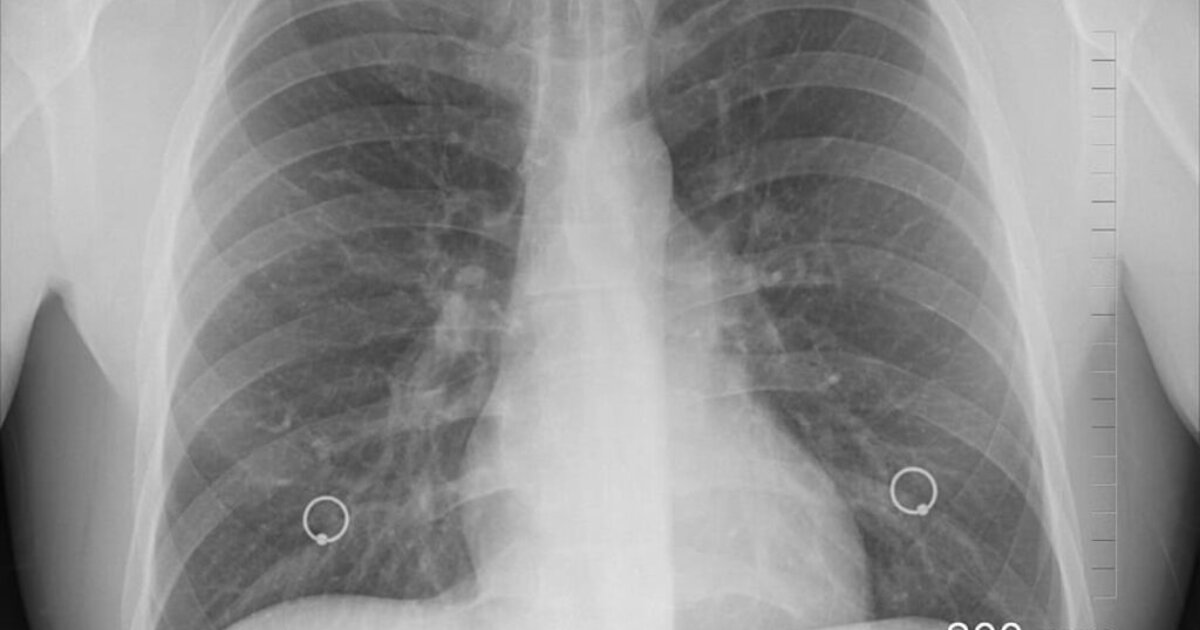

Η ερευνητική ομάδα χρησιμοποίησε αξονικές τομογραφίες περίπου 500 ασθενών με μεγάλους πνευμονικούς όζους για να αναπτύξει έναν αλγόριθμο τεχνητής νοημοσύνης με τη χρήση της ακτινολογίας. Η τεχνική μπορεί να εξάγει σημαντικές πληροφορίες από ιατρικές εικόνες που δεν εντοπίζονται εύκολα από το ανθρώπινο μάτι. Στη συνέχεια, το μοντέλο τεχνητής νοημοσύνης δοκιμάστηκε για να διαπιστωθεί αν μπορούσε να εντοπίσει με ακρίβεια τους καρκινικούς όζους.

Τα αποτελέσματα έδειξαν ότι το μοντέλο τεχνητής νοημοσύνης μπορούσε να προσδιορίσει τον κίνδυνο καρκίνου κάθε όζου με μεγάλη ακρίβεια (AUC 0,87). Σύμφωνα με τη μελέτη, το σύστημα θα πρότεινε την έγκαιρη παρέμβαση για 18 από τους 22 (82%) όζους που στη συνέχεια επιβεβαιώθηκαν ως καρκινικοί.